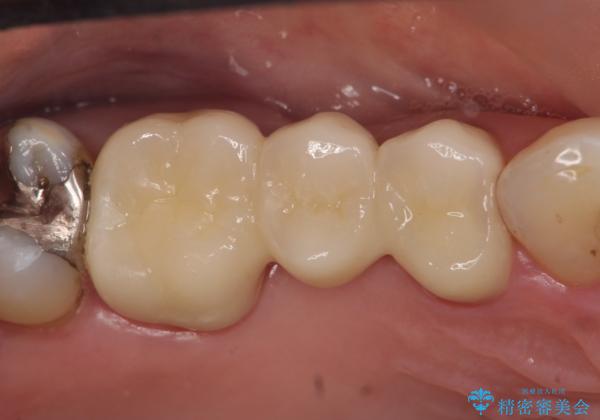

- オールセラミッククラウン…¥100,000×3、仮歯…¥10,000×3費用は治療当時の料金となります

今回用いたオールセラミッククラウンはジルコニアフレームという白い素材の上にセラミックを盛っているため、審美性が非常に高いのが特徴です。

また、ジルコニアは人工ダイヤモンドの材料にも使われているほど高い強度を持っており、そのためオールセラミッククラウンは審美性だけでなく、奥歯やブリッジの補綴も可能とするクラウンです。